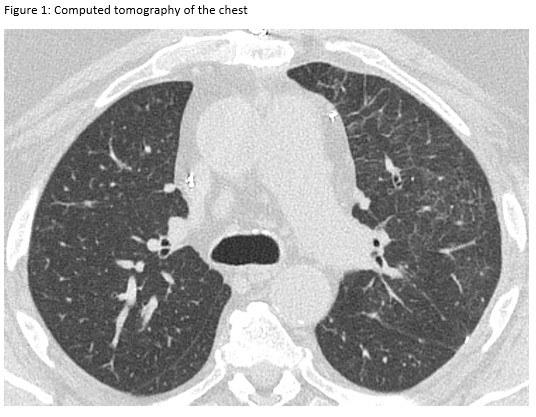

A 72-year-old man presented for evaluation of progressive dyspnea with concern for interstitial lung disease (ILD). He had an extensive cardiac history with prior cardiac bypass surgery and atrial appendage exclusion, followed by multiple subsequent radiofrequency ablations targeting arrhythmogenic foci. His last ablation procedure was three years prior to presentation. He reported reduced exertional tolerance, and was only able to ambulate a few blocks. As a part of his work-up, his local pulmonologist had obtained a high-resolution computed tomography (HRCT) of the chest, which showed abnormalities limited to the left upper lobe (Figure 1). He was treated with antibiotic therapy and corticosteroids but had no improvement so a surgical lung biopsy was performed. These images and biopsies were reviewed at our institution. A representative picture of histology from the biopsy is shown in Figure 2. After his visit to the ILD clinic, a CT angiogram of the chest was obtained and is shown in Figure 3.